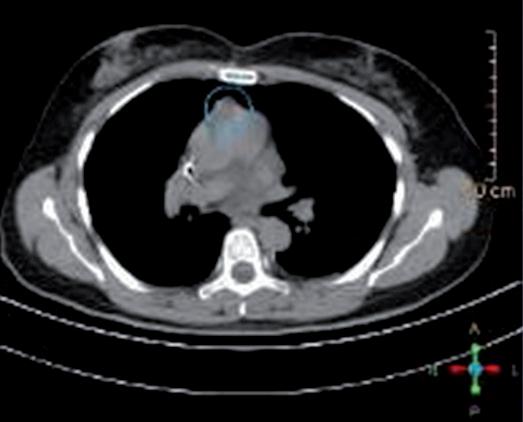

In considerazione della sintomatologia riferita dalla paziente con sensazione di rigidità nucale, difficoltà ai movimenti, dolore base collo, instabilità nella marcia,

parestesie arti inferiori e ipostenia estremità distali esacerbate dal movimento, previa valutazione Multidisciplinare, si completava con RM encefalo + rachide mdc in data 18/07/2023. L’esame confermava la progressione a livello cerebellare destro con comparsa di multiple nodulazioni leptomeningee di natura ripetitiva a livello di tronco encefalico, nervi cranici, superficie midollo spinale, radici cauda e sacco durale (figure 1-3).

Figure 1, 2 e 3. RM encefalo-tronco encefalico-rachide MDC basale pre-trattamento con T-DXd.